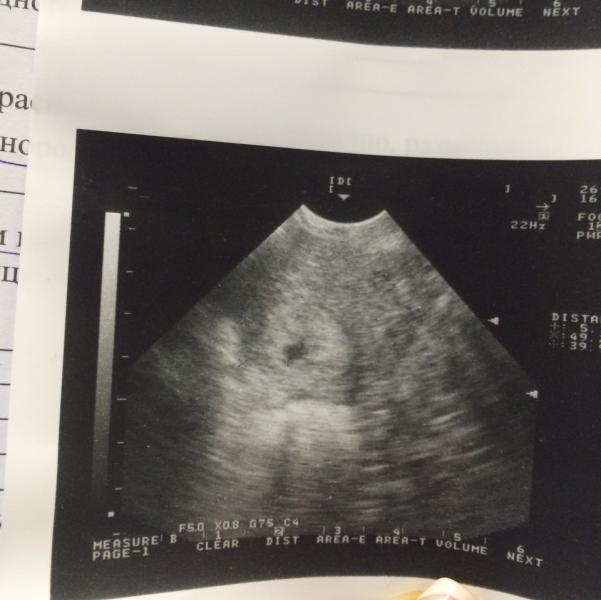

так все время и будет 😂 У меня ещё такая история, сдаю анализы и в ЖК, и в платной. В платной обращают внимание на тревожные значения, в ЖК нет. Сделала УЗИ в ЖК, отмерили нормальную длину шейки поверхностно через живот, в платной сделали как положено трансвагинально ещё, увидели короткую шейку. И так почти во всем.